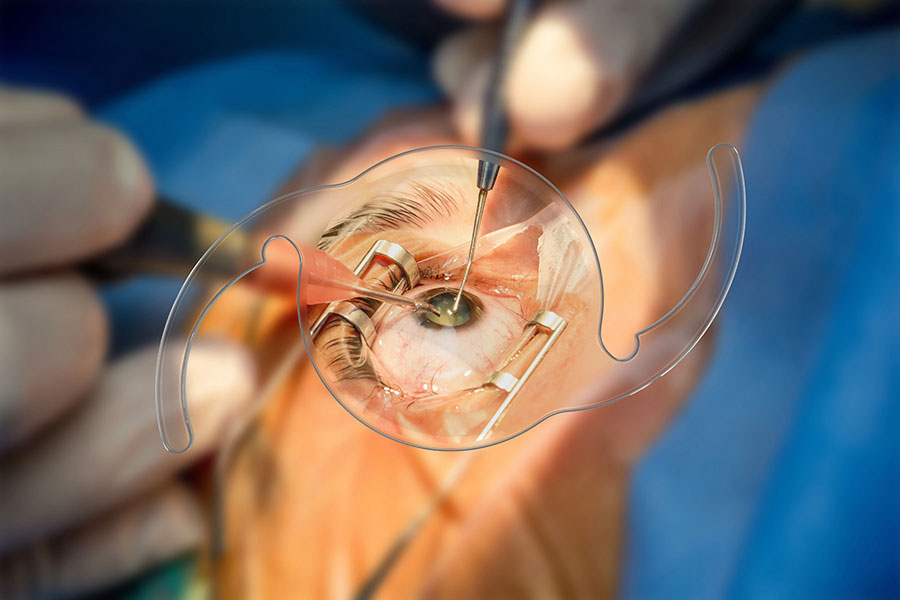

Η τεχνική ένθεσης του ενδοφακού απαιτεί διάνοιξη του επιπεφυκότα, δημιουργία σκληρικών κρημνών στις θέσεις 3 και 9 ώρα. Κατόπιν πρέπει να αφαιρεθεί ο παρεκτοπισμένος ενδοφακός ή τα υπολείμματα του κρυσταλλικού φακού που έμειναν μέσα κατά τη διάρκεια της επιπλεγμένης προηγηθείσας επέμβασης του καταρράκτη. Στη συνέχεια, αν υπάρχει δυνατότητα για ολική υαλοειδεκτομή (χειρουργός οπισθίου ημιμορίου και μηχάνημα με αντίστοιχο μικροσκόπιο), θα είναι προτιμητέο αυτό να γίνει. Αν όχι, τότε ο χειρουργός του πρόσθιου ημιμορίου θα πρέπει να κάνει μία εντεταμένη πρόσθια υαλοειδεκτομή. Και στις δυο περιπτώσεις η ολική ή η μερική αφαίρεση του υαλοειδούς θα ελαττώσει τις πιθανές μετεγχειρητικές ήπιες (μυωψίες, φωταψίες) ή σοβαρές (φλεγμονές, κυστικό οίδημα ωχράς, αποκόλληση του αμφιβληστροειδούς) επιπλοκές.

Κατόπιν από μία κερατική τομή των 2,75 χιλ ενθέτεται ο ενδοφακός. Απαιτείται ένα ειδικό ζεύγος λαβίδων για να μην τραυματισθούν ή αποσπασθούν οι άγκυρες του ενδοφακού κατά τη διαδικασία εξωτερίκευσής τους από τον σκληρό χιτώνα. Οι γνωστές λαβίδες του αμφιβληστροειδούς (serrated ή end- griping) συχνά τραυματίζουν ή ακόμη αποκόπτουν εντελώς την άγκυρα από το σώμα του φακού εάν ασκηθεί υπερβολική πίεση στης λαβές της λαβίδας. Υπάρχουν όμως και οι ειδικά κατασκευασμένες γι’ αυτό τον λόγο λαβίδες (Shariot και Carlevale) που έχουν μαλακές και ευαίσθητες ατραυματικές σιαγόνες. Αυτές είναι οι κατάλληλες για την τοποθέτηση του ενδοφακού. Ο φακός έχει εγκοπές στην άκρη του οπτικού του μέρους που υποδεικνύουν τη σωστή θέση του μέσα στον οπ. θάλαμο (κοίλο μέρος προς τα εμπρός). Έτσι εμποδίζεται η επαφή του φακού με το κορικό χείλος και αποτρέπεται ο κορικός αποκλεισμός και η αύξηση της ενδοφθάλμιας πίεσης. Επίσης, αποφεύγεται η επαφή και ο χρόνιος ερεθισμός της ίριδας με ό,τι αυτό συνεπάγεται.

Οι σκληρικοί κρημνοί ήταν η αρχική τεχνική που συνόδευε την τοποθέτηση του ενδοφακού. Στη συνέχεια ακολούθησε η τεχνική την κάθετων τομών στο ΣΚΟ και οι δημιουργία θυλάκων (τσέπες) εκατέρωθεν της τομής. Μέσα σε αυτούς τους θυλάκους τοποθετούνται οι προεξοχές (αυτιά) της άγκυρας με σκοπό να μην προεξέχουν και διαβρώσουν την Τενόνιο μεμβράνη και τον επιπεφυκότα. Αρκετοί χειρουργοί υαλοειδούς χρησιμοποιούν τις θέσεις των τροκάρ σε θέση απέναντι, 180 μοίρες μεταξύ τους και στο τέλος τις χρησιμοποιούν ως πύλες εξόδου των αγκυρών. Με αυτόν τον τρόπο περιορίζονται οι διεγχειρητικές τομές και ελαττώνεται ο κίνδυνος μετεγχειρητικής υποτονίας. Το μειονέκτημα της τεχνικής είναι πως αφήνει τις άγκυρες ακάλυπτες κάτω από τον επιπεφυκότα, με πιθανότητα μελλοντικής διάβρωσης του επιπεφυκότα. Αυτή είναι μία αρκετά σημαντική επιπλοκή.

Τέλος, εφόσον τοποθετηθεί σωστά ο φακός συρράπτεται ο επιπεφυκότας και σε κάποιες περιπτώσεις και η κερατική πύλη εισόδου του ενδοφακού για περιορισμό της μετεγχειρητικής υποτονίας. Οι χειρουργοί του υαλοειδούς μπορούν με ασφάλεια να πραγματοποιήσουν έλεγχο της περιφέρειας του αμφ/δούς για πιθανές πρΰπάρχουσες ή νεοδημιουργηθείσες ρωγμές του αμφ/δούς. Η ασφάλεια παρέχεται λόγω της σταθερότητας που προσφέρουν οι άγκυρες μέσα στο σκληρό, σε αντίθεση με όλες της άλλες τεχνικές σκληρικής στήριξης. Η απόσταση τοποθέτησης της άγκυρας από το ΣΚΟ, που είχε αρχικά προταθεί από τον Carlevale, ήταν 1,5 με 2 χιλ. Σε αυτήν την απόσταση όμως εμφανίζεται ο κίνδυνος να τραυματισθεί το ακτινωτό σώμα και να έχουμε είτε αιμορραγία είτε χρόνιο ερεθισμό που θα επιφέρει σε απώτερο χρόνο κυστικό οίδημα ωχράς κηλίδας. Ιδιαίτερα σε οφθαλμούς που έχει γίνει ολική υαλοειδεκτομή καλό θα είναι η τομή να γίνεται στα 2,5 ή ακόμη και στα 3χιλ από το ΣΚΟ (προσωπική μου επιλογή) για να ελαχιστοποιούμε την πιθανότητα των προαναφερθέντων επιπλοκών. Στις περιπτώσεις που ο φακός τοποθετείται πιο πίσω, ο υπολογισμός της δύναμης του φακού με τη βιομετρία αλλάζει. Εξαιτίας της υπερμετρωπικής εκτροπής που προκαλείται με την προς τα πίσω μετατόπιση του φακού, επιλέγεται στη βιομετρία ο φακός που να έχει απόδοση -1.00Dpt. Αυτή η διαφορά είναι αρκετή να καλύψει την υπερμετρωπική εκτροπή και να προσφέρει εμμετρωπία.